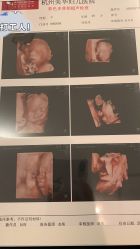

• 杭州贝瑞斯美华妇儿医院·早孕·产检·儿科

• -杭州贝瑞斯美华妇儿医院·早孕·产检·儿科

相册

肚里圆圆 上传于 20-10-29 | 报错